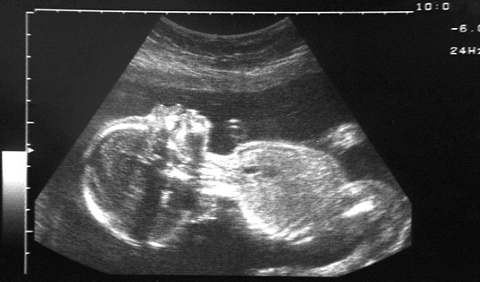

| Hình ảnh thai nhi nữ 19 tuần tuổi mà cặp vợ chồng người Ấn Độ muốn chối bỏ |